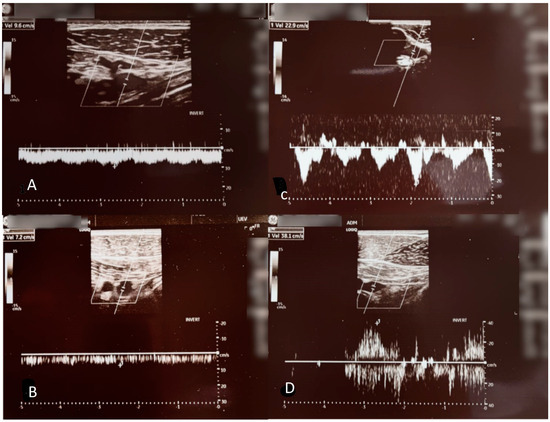

2. Case Presentation